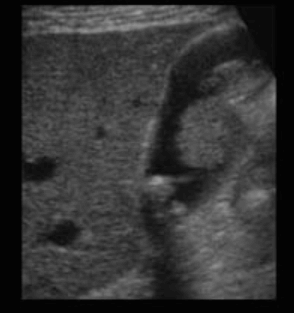

- wall 비후가 심할 때 악성과 감별이 어렵다 (도플러를 사용하여 감별)

- 국소형 (fundal type): 벽비후가 저부에 국한되어 있다. 암호발부위이며 doppler 검사를 필수로 시행한다.